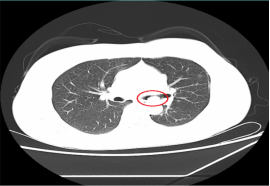

近日,一位患支氣管腫瘤患者到我院呼吸內(nèi)科治療,檢查時(shí),其腫瘤幾乎已經(jīng)完全堵塞氣管管腔,若不及時(shí)手術(shù),隨時(shí)可能發(fā)生呼吸衰竭。

情況危急,醫(yī)生立即為其抽取動(dòng)脈血化驗(yàn)并給予高流量吸氧等,但患者呼吸困難的癥狀緩解不明顯,必須及時(shí)將腫瘤切除。“如果按照傳統(tǒng)的手術(shù)方式,需將患者氣管切開,組織損傷性高、流血量多。由于患者腫瘤貼近降主動(dòng)脈,切除過程中將伴有大出血的風(fēng)險(xiǎn)。”劉碧翠說,隨著我院內(nèi)鏡技術(shù)的發(fā)展,對(duì)于這樣的重癥患者,可以利用呼吸內(nèi)鏡迅速切除腫瘤,清理氣道內(nèi)局部的壞死組織、分泌物并予以止血處理。

科室介入團(tuán)隊(duì)經(jīng)過精心準(zhǔn)備后,立刻為患者實(shí)施內(nèi)鏡介入手術(shù),將氣道內(nèi)腫物切除干凈。手術(shù)僅用時(shí)2小時(shí),患者沒有發(fā)生大出血,很快便恢復(fù)出院。此次手術(shù)的成功開展,充分體現(xiàn)了呼吸內(nèi)科對(duì)此類疑難危重氣道疾病患者的救治能力。